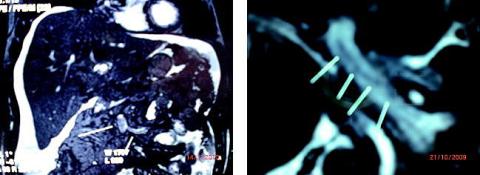

En magnetisk resonans (MR)-skanning viste en lang, tynd trombe med randflow. Der blev ikke fundet øsofagusvaricer ved gastroskopi. Man påbegyndte antikoagulans (AK)-behandling med lavmolekylært heparin og warfarin, men uden effekt på ascitesmængden. Der blev derfor anlagt transjugulær intrahepatisk portosystemisk shunt (TIPS), hvorefter ascitestendensen forsvandt. I forbindelse med TIPS-anlæggelsen blev patienten atter UL-skannet, og da var portatrombosen væk. Levercirrose disponerer til portatrombose. FIBDP er mindre egnet til diagnostik, da det altid er forhøjet ved cirrose. Mistanken opstår ved Doppler-UL-skanning, som her. Computertomografi med kontrast i portalvenefasen eller som her MR-skanning kan visualisere disse tromber. Da tromben var frisk, var det umagen værd at se, om den forsvandt under AK-behandling. Øsofagusvaricer kan opstå på få måneder, ascites er til stede hos ca. 40% med portatrombose, men kan være helt fraværende.

Selvom CT med kontrast er den nemmeste måde at fremstille portatromboser på, er MR i øvede hænder formentlig lige så godt og i hvert fald bedre rent strålehygiejnisk.

Billederne viser en MR-oversigt uden kontrast af leveren, hvor tromben i vena portae er markeret, og vena portae, hvor den stiger op i leveren efter at være dannet af vena lienalis og vena mesenterica med markering af en lang tynd trombe, hvor blodlegemerne ved deres flow virker som kontrast.